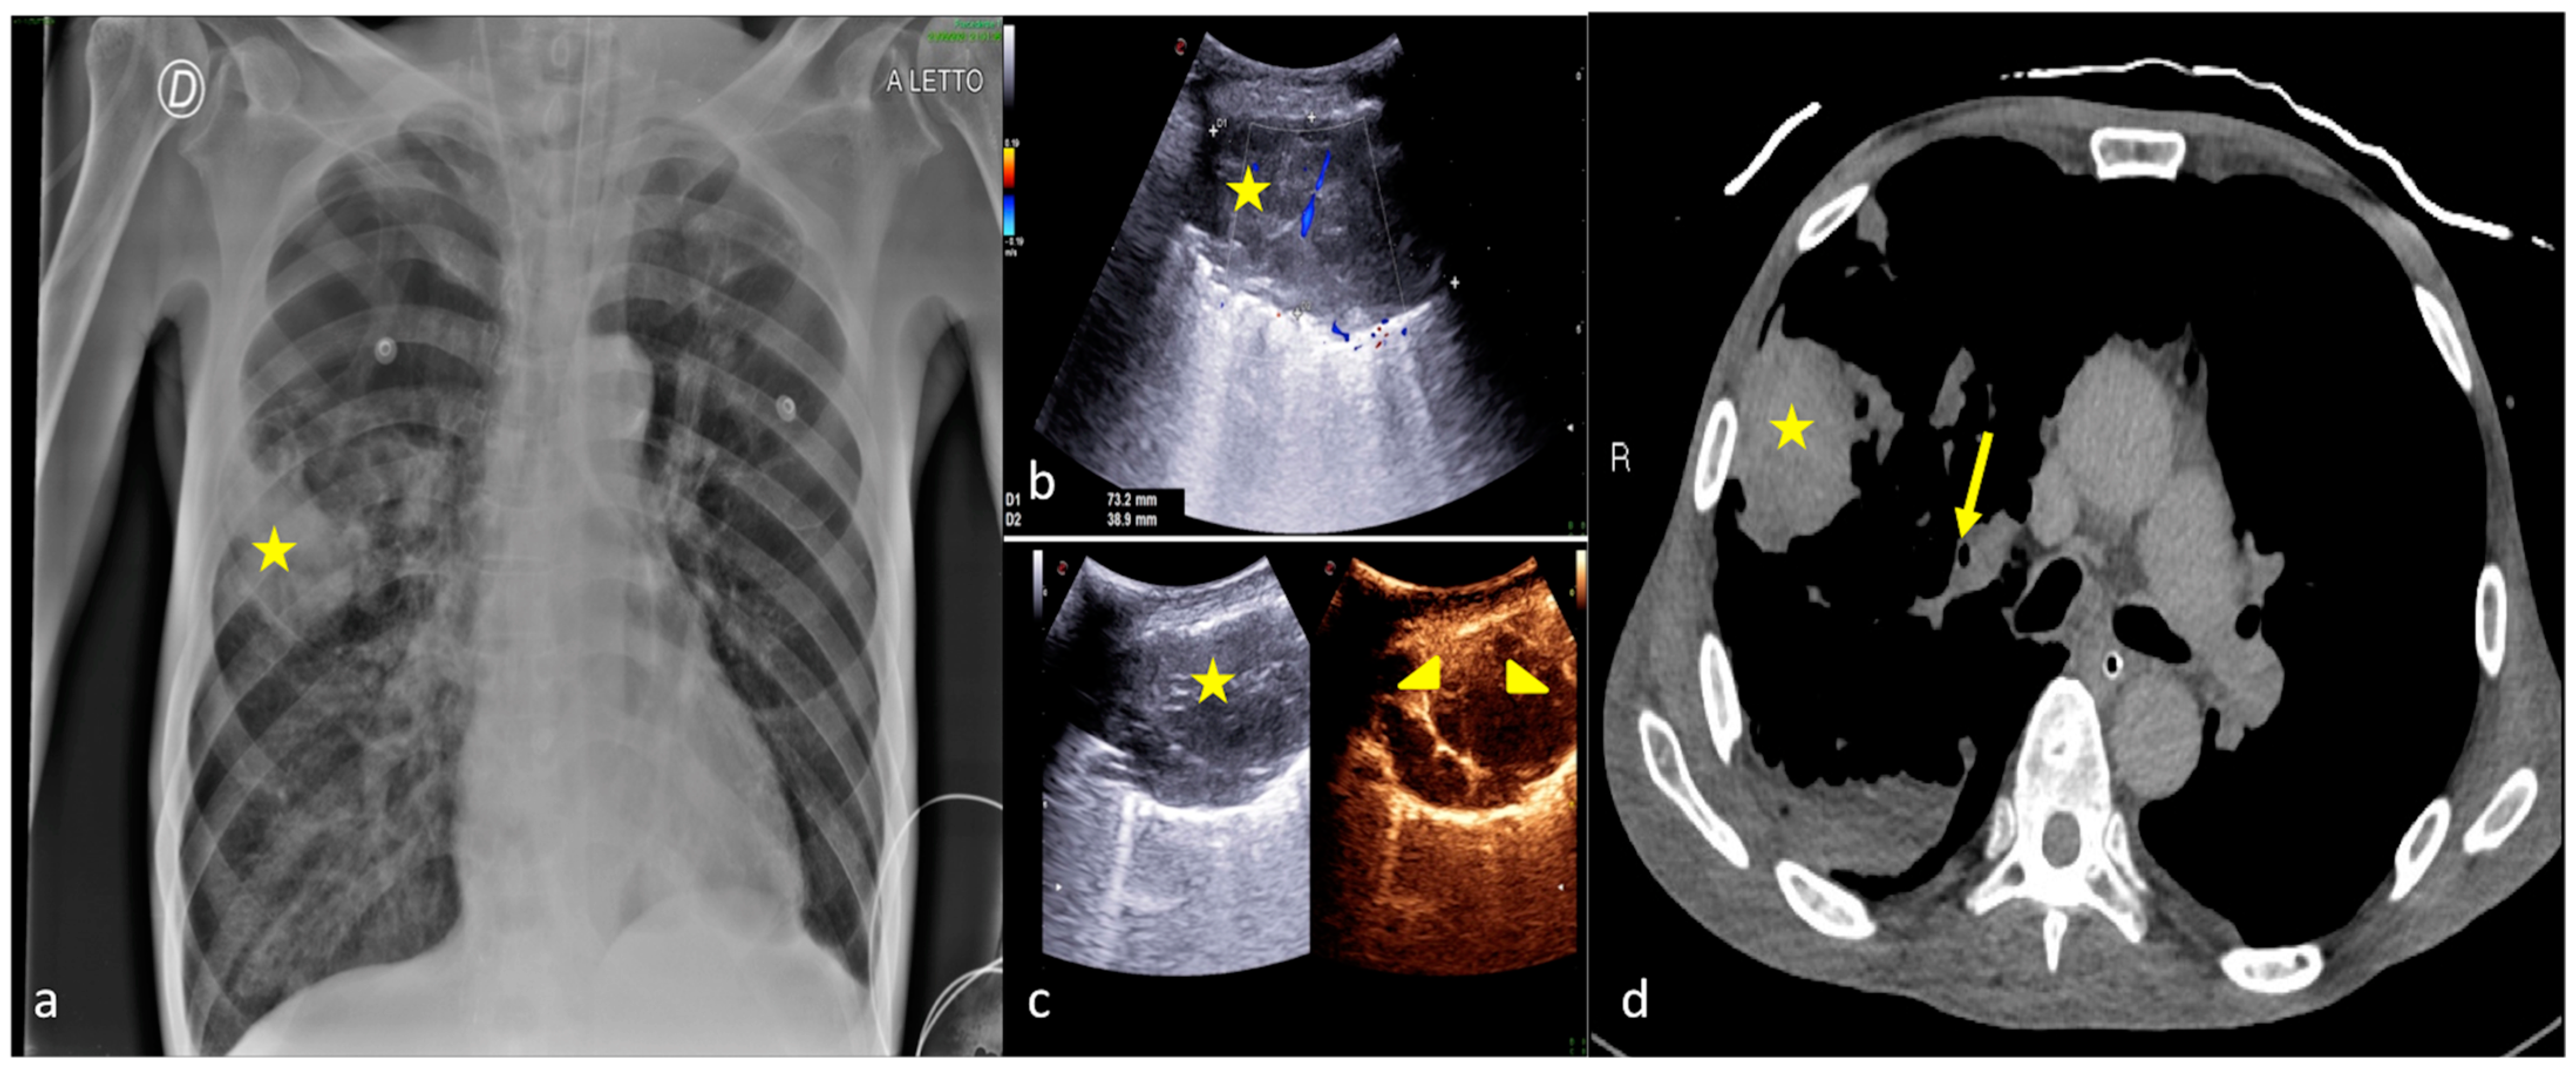

2.3. Pleural Effusion

- Shao, R.-J.; Du, M.-J.; Xie, J.-T. Use of lung ultrasound for the diagnosis and treatment of pleural effusion. Eur. Rev. Med. Pharmacol. Sci. 2022, 26, 8771–8776. [Google Scholar] [CrossRef]

- Brogi, E.; Gargani, L.; Bignami, E.; Barbariol, F.; Marra, A.; Forfori, F.; Vetrugno, L. Thoracic ultrasound for pleural effusion in the intensive care unit: A narrative review from diagnosis to treatment. Crit. Care 2017, 21, 325. [Google Scholar] [CrossRef]

- Kitazono, M.T.; Lau, C.T.; Parada, A.N.; Renjen, P.; Miller, W.T. Differentiation of Pleural Effusions From Parenchymal Opacities: Accuracy of Bedside Chest Radiography. Am. J. Roentgenol. 2010, 194, 407–412. [Google Scholar] [CrossRef]

| Pleural Effusion | Supine chest radiography may reveal abnormality when the amount of fluid reaches 175–525 mL, which is higher than that for upright chest radiography. | US may detect 5–20 mL of pleural fluid with an overall sensitivity of 89–100% and specificity of 96–100%. |